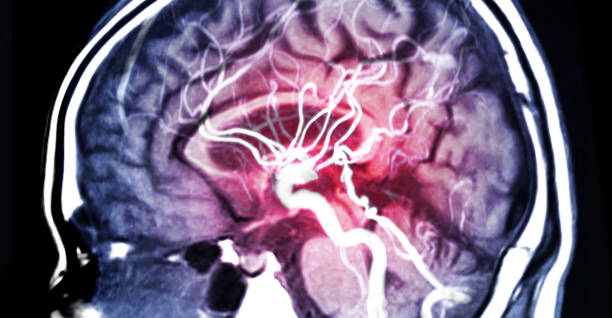

뇌졸중

뇌동맥류가 크거나 위치가 민감한 경우 뇌졸중을 초래할 수 있습니다. 뇌졸중은 뇌의 혈관에 혈전이 생기거나 출혈이 발생하여 뇌의 기능이 일시적으로 또는 영구적으로 손상되는 상태를 말합니다. 이러한 증상은 뇌동맥류의 위치와 크기에 따라 발생할 수 있으며, 응급 상황이므로 즉각적인 치료가 필요합니다.